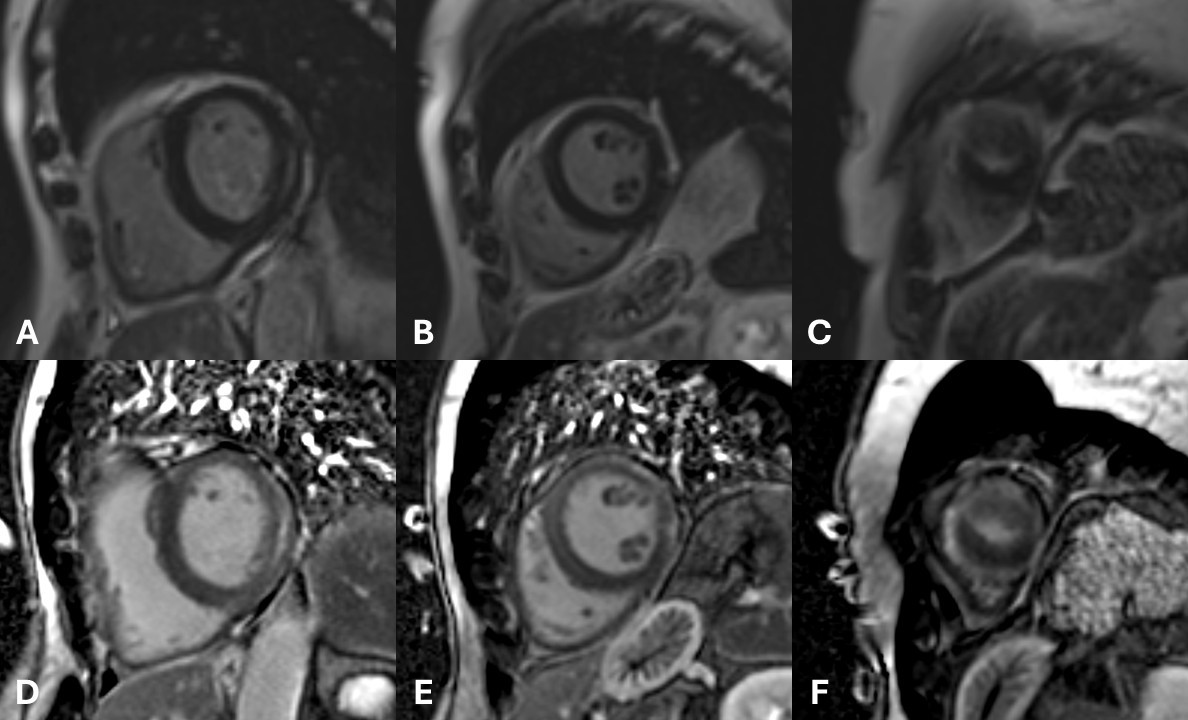

Top row (A-C): Short-axis PSIR images done last 2023 initially showed subtle low intensity mid-myocardial LGE involving the interventricular septum and sub-epicardial distribution at the lateral wall extending to the apical LV walls. Bottom row (D-F): Short-axis PSIR images from the recent study show progression of LGE with extensive involvement in a mid-myocardial and sub-epicardial pattern.